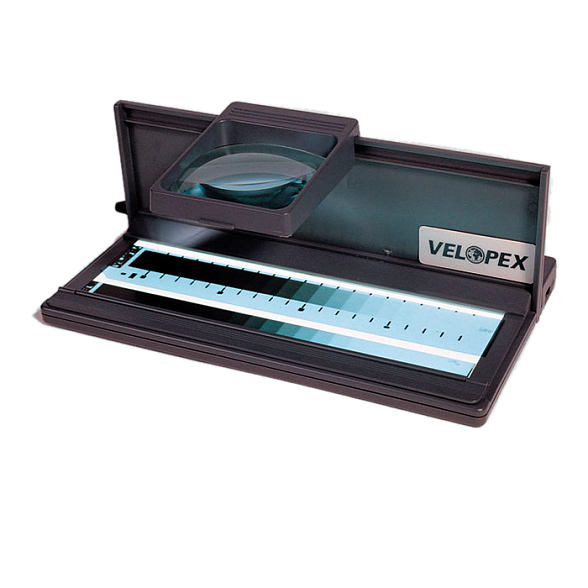

Daray DX4101LED Single Panel X-Ray Film Viewer - негатоскоп

Негатоскоп Daray DX4101LED: Профессиональная оценка рентгеновских снимков

Негатоскоп Daray DX4101LED — это современный и надежный просмотровый стол, предназначенный для точной и комфортной интерпретации рентгеновских, МРТ, КТ и других медицинских снимков. Он заменяет устаревшие люминесцентные модели, предлагая врачам-рентгенологам, травматологам, стоматологам и ветеринарам совершенный инструмент для ежедневной диагностической работы.

Однородная яркая LED-подсветка без мерцания и горячих точек обеспечивает идеальные условия для чтения даже самых плотных участков снимка, снижая нагрузку на зрение и минимизируя риск диагностических ошибок.

Области применения

Daray DX4101LED незаменим везде, где требуется детальный анализ медицинских изображений на пленке: в государственных и частных поликлиниках, больницах, травмпунктах, стоматологических центрах, ветеринарных клиниках, а также в научно-исследовательских учреждениях.